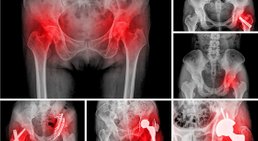

- Hüftgelenksersatz bei Arthrose (minimal-invasiv, AMIS Methode)

Hüftprothese

Neben dem Knie zählt die Hüfte zu einem der am häufigsten orthopädisch behandelten Gelenke. Die Hüfte kann von vielen verschiedenen Krankheiten betroffen sein,...